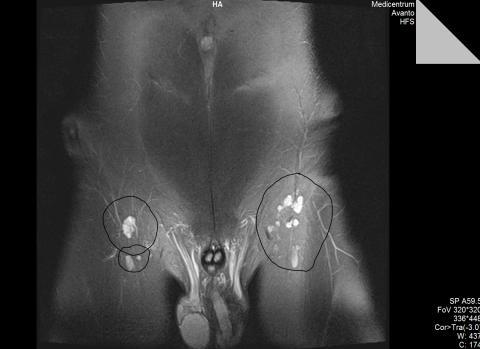

Dobrý deň , mal som veľké bolesti bedrovej kosti na pravej strane ,a tak som zašiel ku svojmu doktorovy.Ten ma poslal na vyšetrenie ku ortopédovy,neskôr som išil na rentgen ... Výsledký boli negatívne,na fotke sa nič nenašlo ... Ortopéd povedal že to môže byť buchnuté alebo niečo také .. Povedal aby som si dal mesiac pauzu,aby soim oddychoval a nezaťažoval nohu ... Po mesiaci mi kázal prísť na kontrolu . Prišiel som a bolesti pretrvávali stále . Nenašiel žiadne možnosti a tak ma poslal na magnetickú rezonanciu aby sa dozvedel viac . Sám doktor nevedel čo tomôže byť a chcel vedieť čo to je ... Prišiel som s magnetickej rezonancie a tie isté bolesti sa mi preniesli na druhú stranu bedrovej kosti čiže na pravú ... Ale to je jedno ... :D Dostal som CD z magnetickej rezonancie a na fotke boli odfotené pekne bedrá a na bedrach MALĚ BIELE FĽAKY !!! Tie ma zaujímajú najviac a chcel by som vedieť čo to môže byť ? Jedná sa o niečo vážne ? Je to len dáky sval alebo niečo čo nieje vážne? ( fotky prikladám k tomuto ) S CDčkom pôjdem ku doktorovy až v pondelok a do vtedy chem ohľadom toho niečo zistiť ... Za všetko Ďakujem ...

Dobrý den, magnetická rezonance je speciální zobrazovací metoda, ze které neumí číst každý radiologie, natož lékař V první řadě, to co máte zakroužkované, jsou spíš třísla než bedrová kost (česky kyčelní kost).Jinak dle mého názoru jde o zobrazené lymfatické uzliny